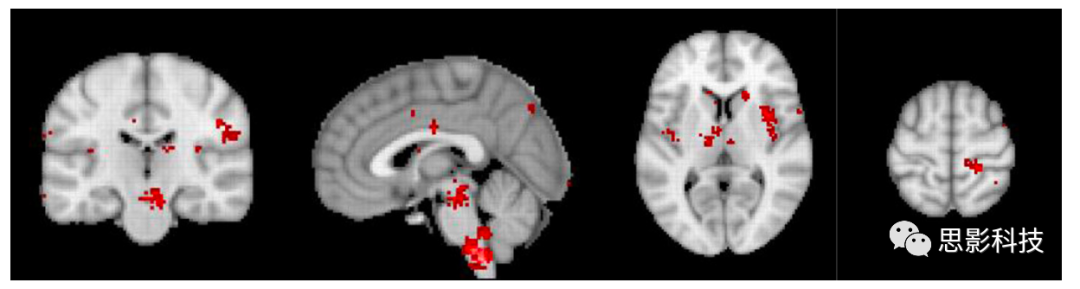

图 3. 慢性疼痛的Neurosynth元分析。前至膝下前扣带回皮层成分缺失,暗示慢性疼痛与失去的抑制有关。修改自De Ridder等人的参考文献(29)。

这一元分析进一步指出,在慢性疼痛中,前至膝下前扣带回成分的缺失可能与疼痛的持续和难以控制有关。这一发现强调了在慢性疼痛治疗中,恢复或增强抑制机制可能是一个关键方向。

使用机器学习,已经开发出了具有94%准确度的急性疼痛的fMRI神经标志(71)。神经特征包括双侧背侧后岛叶、次级体感皮层、前岛叶、腹外侧和内侧丘脑、下丘脑和背侧前扣带皮层(71),换句话说,就是侧疼痛通路和中央疼痛通路的组成部分。与神经合成元分析关于(急性)疼痛的相反,92个关于慢性疼痛的研究的相同分析并没有显示下行疼痛抑制通路中的任何活动。但侧疼痛通路和中央疼痛通路的参与仍然存在。神经合成元分析的比较明确地表明,慢性疼痛可能是由于疼痛抑制通路激活不足,而不是上行疼痛通路激活增加的结果。这与早期报告一致,即慢性疼痛与丘脑抑制丧失有关(72)(图3)。在一种广泛的慢性疼痛形式——纤维肌痛中,pgACC到rACC的不足已经得到了详细的描述(63, 73, 74)。一种类似的纯粹数据驱动的方法也识别出了具有相似准确度93%的慢性疼痛的EEG神经标志,几乎涉及相同的区域。